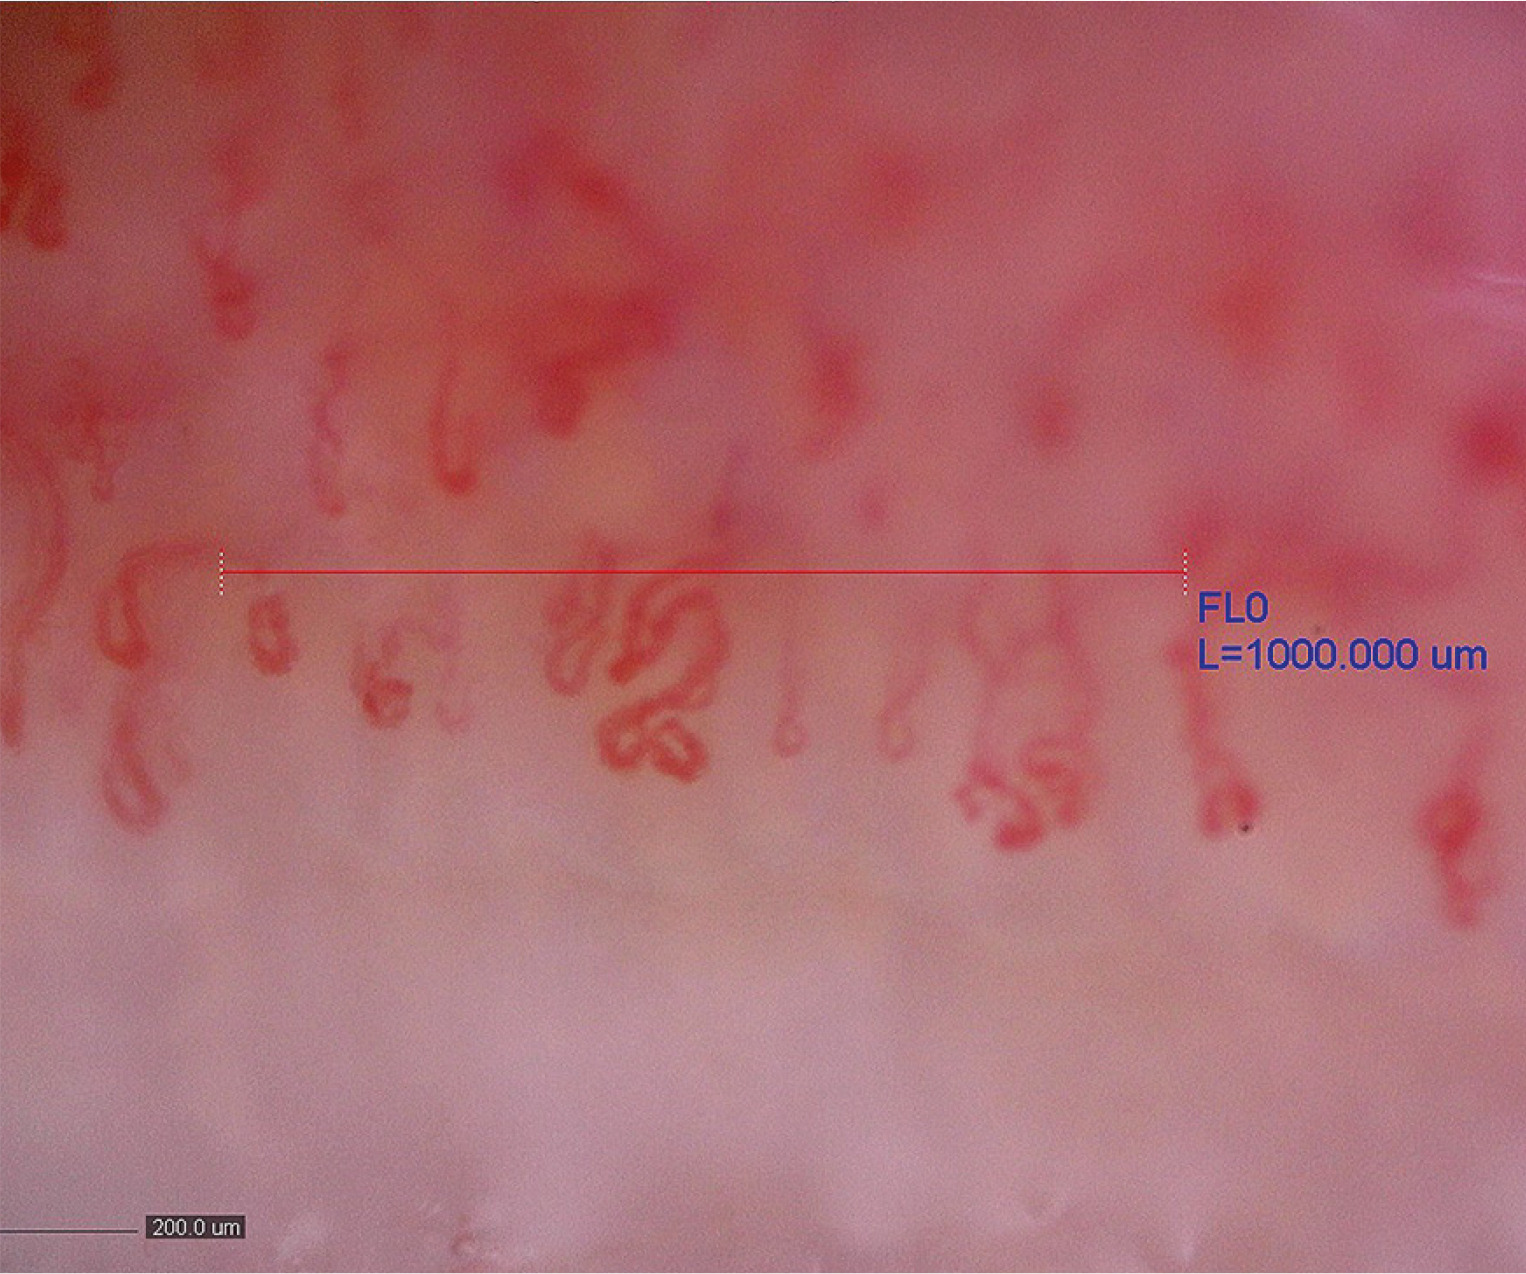

In addition to SSc, capillaroscopic examination is helpful in the diagnosis and monitoring of “scleroderma spectrum” diseases, which include dermatomyositis (DM), mixed connective tissue disease (MCTD), or undifferentiated connective tissue disease (UCTD) [8]. In systemic connective tissue diseases other than SSc, particularly in “scleroderma spectrum” diseases, capillaroscopic images may present normal capillaroscopic findings, nonspecific abnormalities, or “scleroderma patterns” [1]. According to the recommendations of Cutolo et al. [5], capillaroscopic changes characteristic of SSc that meet the criteria of the “scleroderma pattern” occurring in other diseases of the “scleroderma spectrum” are referred to as scleroderma-like microangiopathy. Capillaroscopic examination has been shown to be a valuable tool for assessing microcirculation disorders in idiopathic inflammatory myopathies (IIMs), especially in those subtypes in which vascular damage plays a significant role, namely in DM, or anti-synthetase syndrome [9]. Scleroderma-like microangiopathy occurs in about 20–40% of patients with IIMs, more often in DM than in polymyositis [10]. The capillaroscopic changes that dominate in the course of DM are increased neoangiogenesis and reduction in capillary density, with a relatively small number of avascular areas. The presence of branching giant vessels is also characteristic (Fig. 1). Often, in 1 patient, different capillaroscopic changes are found in different fingers [10]. Due to significant differences in capillaroscopic images in patients with SSc, compared to DM patients, some researchers suggest that the term “microangiopathy in the course of DM” should be used instead of “scleroderma-like microangiopathy” [11]. Many studies have emphasized that capillaroscopic images in the course of DM are very diverse [11, 12]. The analysis of 2 comparative studies on patients with SSc and DM shows that patients with DM seem to demonstrate less capillary loss than patients with SSc. In the scleroderma group, progression of microangiopathy from “early” to “late” stages over time is typical, which is not as pronounced in patients with DM [11, 12]. Specifically, comparing patients with DM with SSc patients with “early”, “active”, or “late” microangiopathy, DM patients generally show a smaller reduction in capillary density than patients with SSc, although they still show greater reduction than patients with early scleroderma microangiopathy in the course of SSc [11]. Interestingly, in the course of inflammatory myopathies, the “scleroderma-like” pattern, defined as a capillary pattern showing mixed microvascular markers of the scleroderma patterns, but not proportionally fitting the definition for the single “early,” “active,” or “late” pattern, was also found to be discriminatory between patients with IIMs and patients with SSc [13]. For example, in the course of inflammatory myopathies, a significant reduction of capillary density below 4 capillaries per linear millimeter may coexist with the presence of giant vessels, allowing such changes to be defined as a “scleroderma-like” pattern. In the course of microangiopathy in SSc, giant loops never co-occur with extreme reduction of the capillary density; namely, giant loops are characteristic of the “early scleroderma pattern,” whereas extreme vessel reduction without the presence of giant capillaries is characteristic of the “late scleroderma pattern” [1].

Fig. 1

Scleroderma-like microangiopathy in the course of dermatomyositis (200× magnification).

Source: Ewa Wielosz archive images.